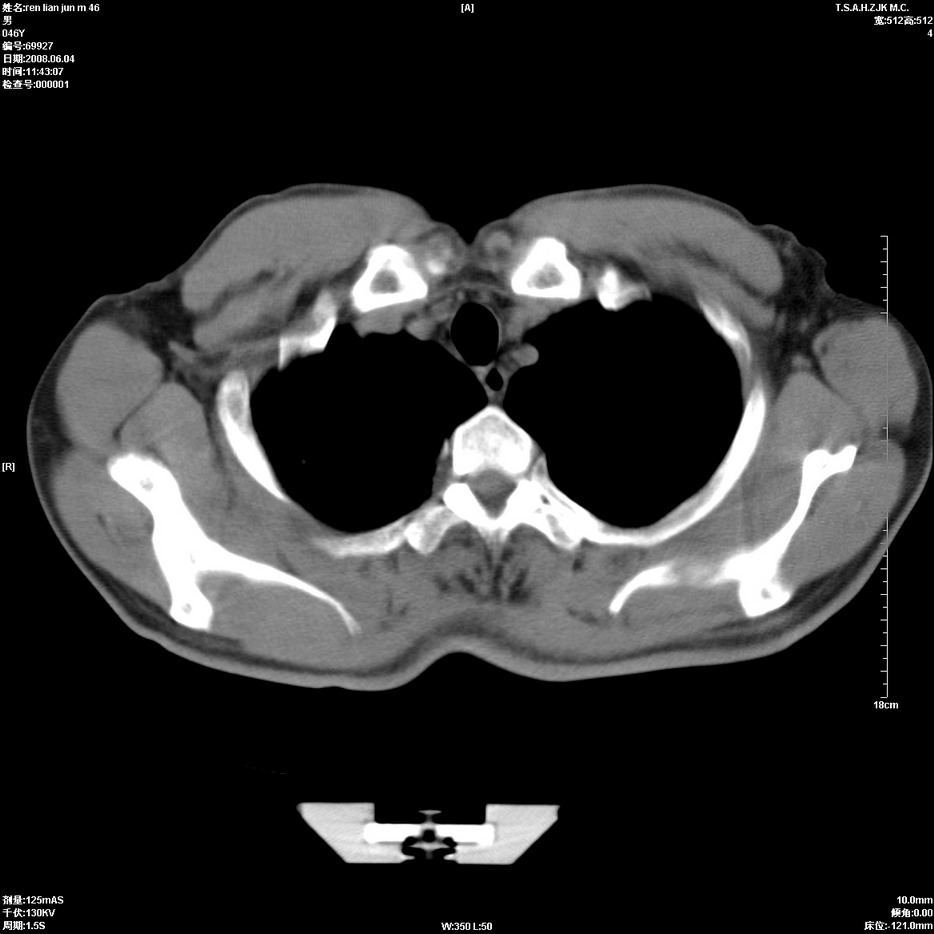

以下是引用形影不离在2008-6-5 19:18:00的发言:[br]右肺中心型肺癌并纵隔及左侧腋窝淋巴结转移,颅内应做增强检查。